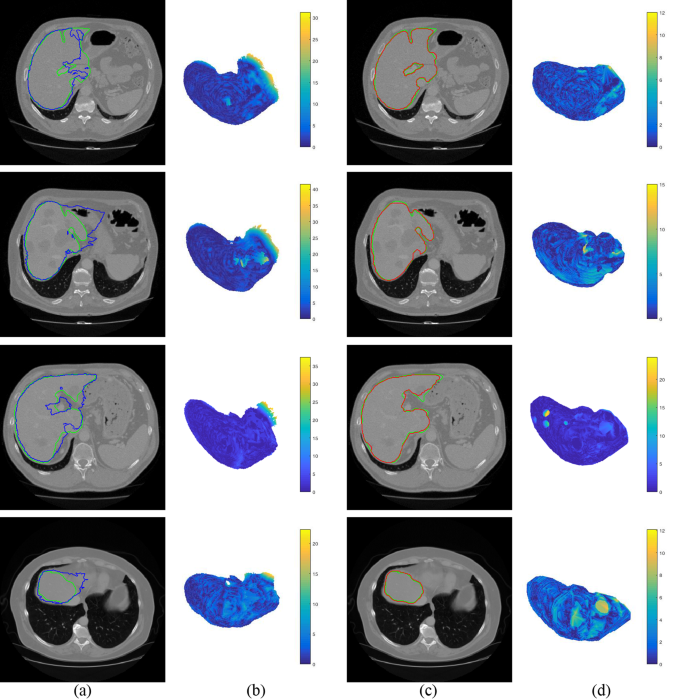

As can be seen in the 5th row of Table 2, initial shape of liver is far from final segmentation. Figure 8 shows the initial and final segmentation results with four difficult cases. The first row in Fig. 8a,c show that intensities of stomach and liver are almost same. MAS depending on intensity only can be applied to reach most of the target boundary, except the edges intersecting with two organs. After using multi-dimensional graph cut, the maximal distance to target boundary decreases from 32.32 mm to 12.04 mm (see the first row in Fig. 8b,d). The second row in Fig. 8a,c shows that there are some tumors in this CT image. This difficulty leads to 41.63 mm of the maximal distance to target boundary on initialization stage. After the initial shape is adapted, the maximal distance is decreased to 15.08 mm (see the second row in Fig. 8b,d). The third row in Fig. 8a,c shows that separating the sharp structures and the vessel is challenge. The maximal distance through coarse-to-fine segmentation decreases from 37.48 mm to 26.83 mm (see the third row in Fig. 8b,d). It can be observed from the fourth row of Fig. 8a,c that the boundary between liver and heart is hard to be distinguished. The maximal distance to target boundary is 11.98 mm on final segmentation, as well as that of initialization is 27.28 mm (see the fourth row in Fig. 8b,d).

Liver initial and final segmentation results with four difficult cases. The ground truth is shown in green curves. (a) Initial segmentation (blue curves). (b) Surface distance between initial segmentation to ground truth. (c) Final segmentation (red curves). (d) Surface distance between final segmentation to ground truth.